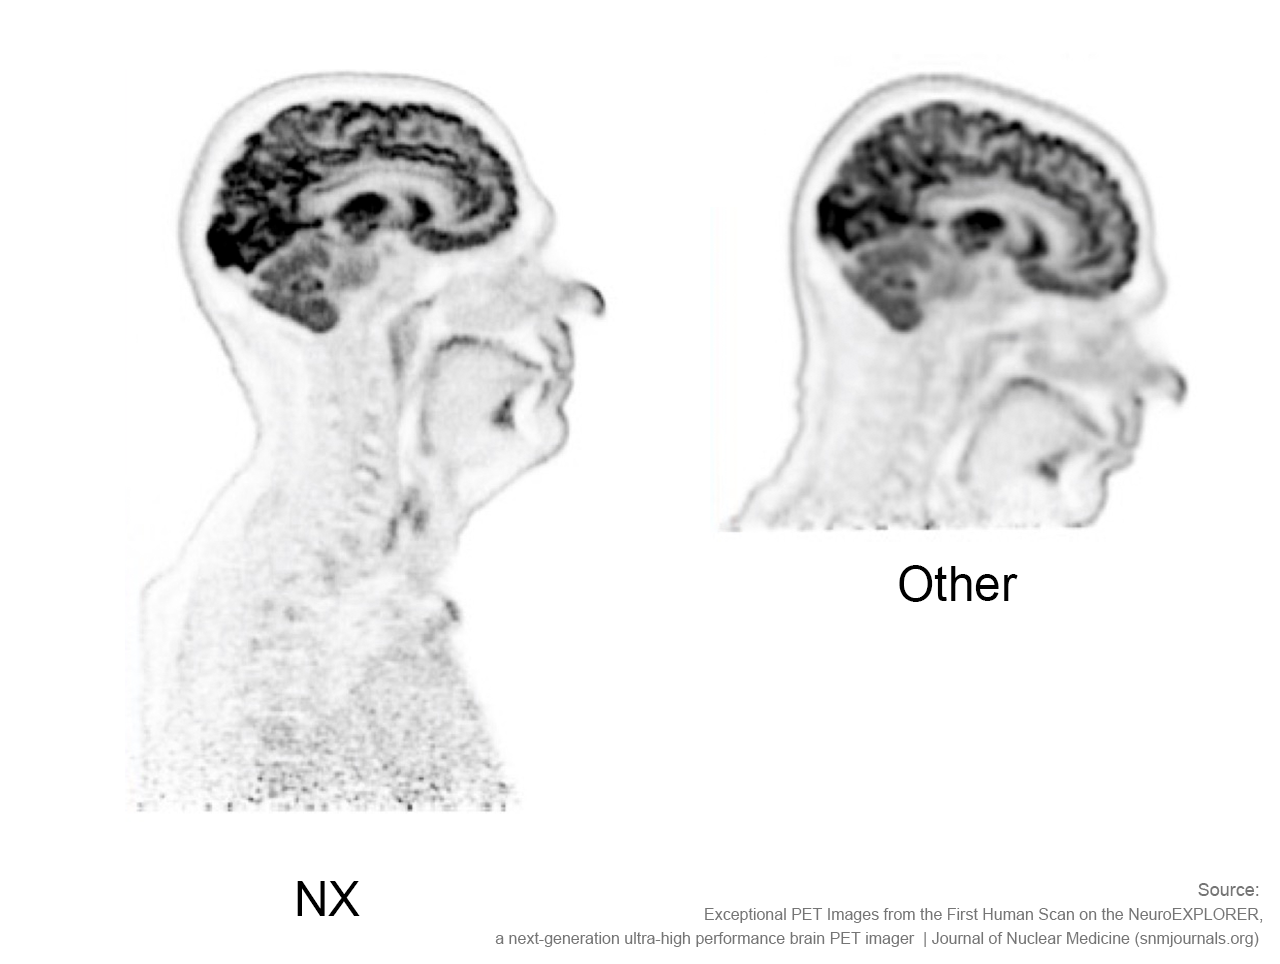

NeuroExplorer (NX)产出的脑部影像图与其他设备产出的脑部影像图对比

搭载长达50cm的轴向视野,可捕捉到从头顶到肩部区域的完整图像,确保其能够监测该区域的血管和示踪剂输送到大脑的动态情况,这一卓越性能助力NX成为脑科学领域研究强有力的工具。

NeuroExplorer (NX) 产出到从头顶到肩部区域的完整图像